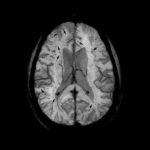

Study: New cause of brain bleeds identified — (Details)

A team of researchers including UCI project scientist Rachita Sumbria, PhD and UCI neurologist Mark J. Fisher, MD have provided, for the first...